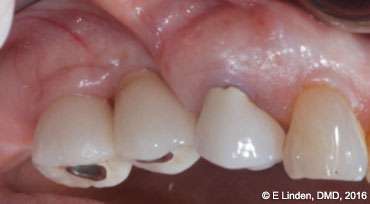

Bone sounding: Once anesthesia took effect, bone sounding was performed in order to precisely determine the bone topography (Figure 6). This step is crucial with the closed technique. The data obtained guides the clinician as to how far the laser tip needs to go into the pocket. The clinician will then move the laser tip staying 1 mm-2 mm away from the bone.

Figure 6: Preoperative bone sounding (under local anesthesia) was needed to determine the bone topography